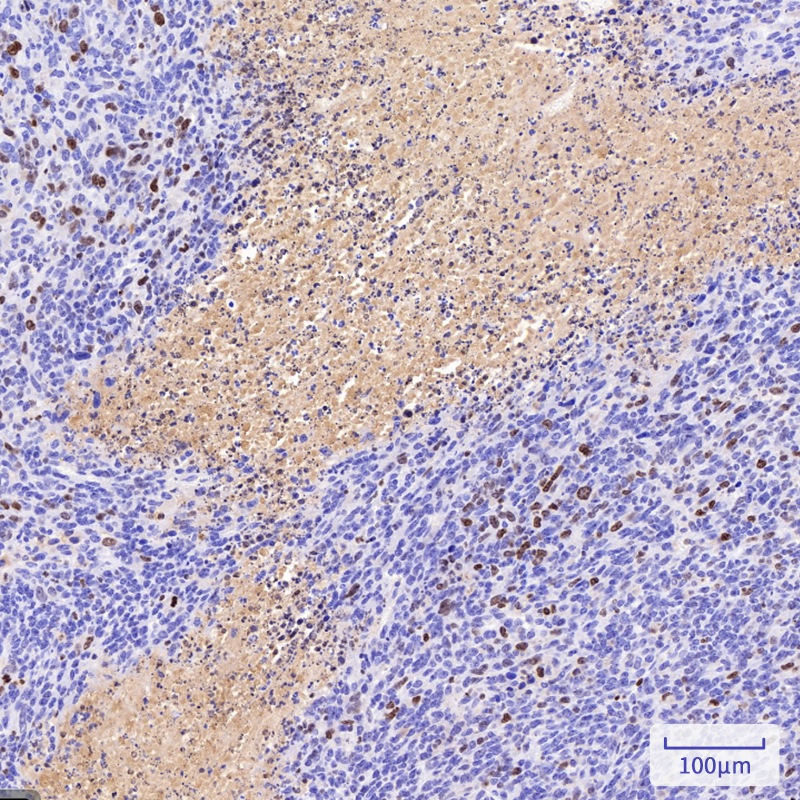

The Ki-67 protein (also known as MKI67) is a cellular marker for proliferation. Ki67 is present during all active phases of the cell cycle (G1, S, G2 and M), but is absent in resting cells (G0). Cellular content of Ki-67 protein markedly increases during cell progression through S phase of the cell cycle. Therefore, the nuclear expression of Ki67 can be evaluated to assess tumor proliferation by immunohistochemistry. It has been demonstrated to be of prognostic value in breast cancer. In head and neck cancer, several studies have reported an association between high proliferative activity and poorer prognosis.

Immunohistochemistry analysis of paraffin-embedded Human liver cancer in Chimera mouse using Ki67 antibody. High-pressure and temperature Sodium Citrate pH 6.0 was used for antigen retrieval.